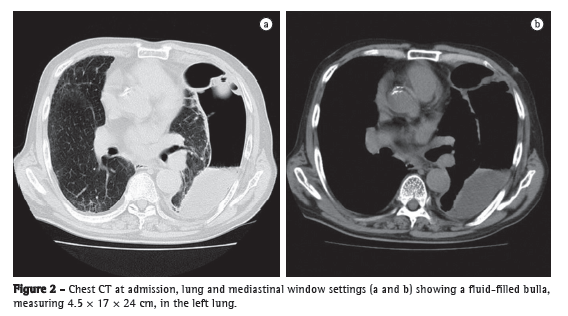

A 79-year-old man sought treatment in the emergency room, complaining of a 3-month history of persistent fever, chest pain, and general fatigue. He had a smoking history of 60 pack-years and had been a heavy drinker of Japanese sake (180 mL/day) for the past thirty years. Laboratory test results indicated severe inflammation, and a chest X-ray showed a giant bulla with a diameter of 24 cm in the left lung (Figure 1a). By his own account, he had no history of abnormalities on X-rays, and his latest medical check-up, conducted in the preceding year, had produced no abnormal findings (Figure 1b). CT scans of the chest revealed that the bulla was fluid-filled and measured 4.5 × 17 × 24 cm (Figure 2). The patient was diagnosed as having a lung abscess and was admitted to our hospital.

the lung parenchyma, resulting in the formation of blebs and bullae.(2) Fain et al. attributed the formation of giant bullae to smoking, which decreases the blood flow to the alveoli.(2) In the case presented here, the giant bulla appeared to have grown rapidly, given that no abnormalities had been found during the medical check-up conducted in the preceding year. We presume that the check-valve mechanism related to the tumor in the left lower bronchus promoted the growth of the bulla.